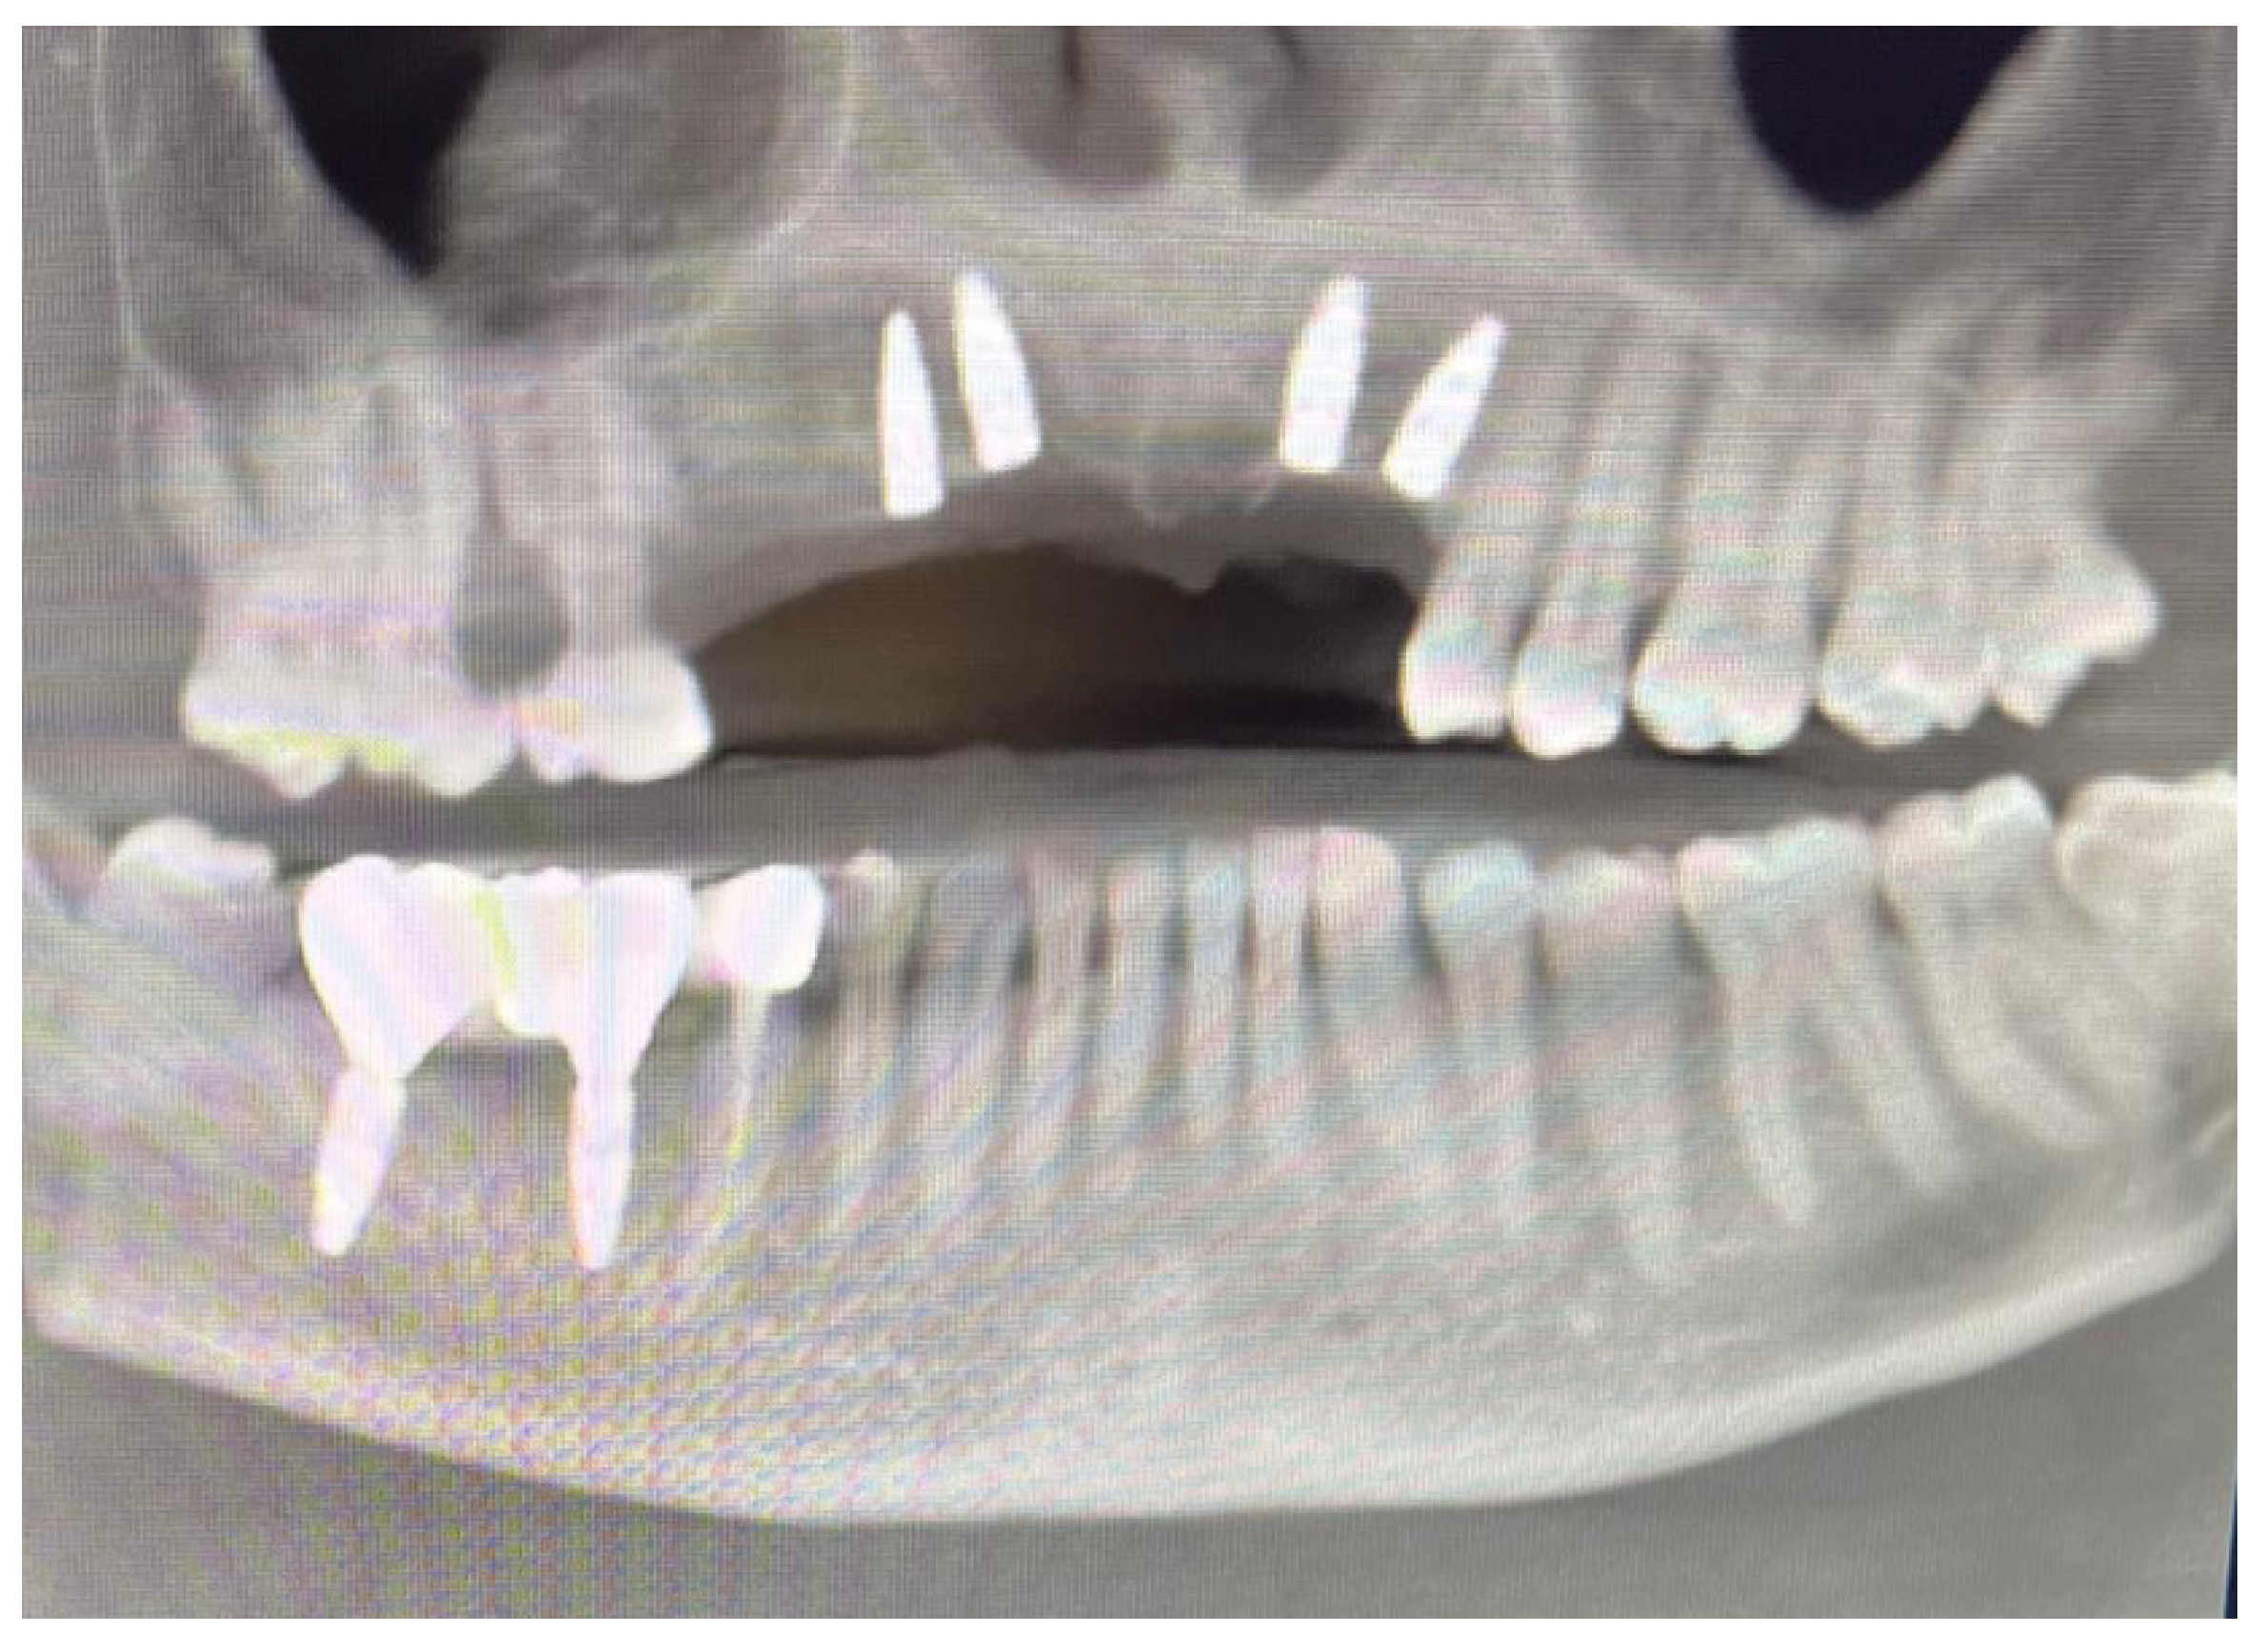

Based on previous experience and the speed of their development, in January 2023, it was decided to extract teeth 14 and 15, 46 and 47, decontaminating the alveoli, regenerating with PRF (in order to promote healing of the defect) and heterologous bone. So, the site was treated with a mix of Bio-Oss granules 25 (Geistilich Bio-Oss-Geistlich Pharma AG, Wolhusen, Switzerland), autologous bone chips, platelet-rich fibrin (PRF), and collagen membranes (45% Bio-Oss 25, 45% PRF, 10% autologous bone chips). Simultaneously, four implants (3.6 × 10 mm, Biotech Dental, Allée de Craponne, Salon de Provence, France) were inserted in the upper edentulous area, completely submerging them. However, an initial rejection of three of the four implants was observed (about 20 days after insertion), which made it necessary to remove them, decontaminate them with dye-free photodynamic therapy, and reinsert them 120 days later, when the implants were also inserted in areas 46-47 (3.6 × 10 mm and 4.2 × 10 mm, Biotech Dental, Allée de Craponne, Salon de Provence, France) in June 2023 (Figure 7).

In June 2024, the implants were inserted in areas 16 and 17. Three months after the insertion of the last implants in 16-17 (4.2 × 10 mm and 4.2 × 8 mm, Biotech Dental, Allée de Craponne, Salon de Provence, France), it was possible to proceed with the digital impression-taking to proceed with a temporary prosthesis in PMMA (Figure 9) after a radiographic control (Figure 10).

Figure 10. OPT after all implant placements, in July 2024.